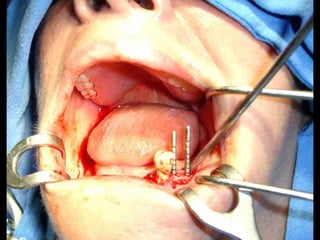

Segundo tiempo quirúrgico para aplicar la estructura.

Estructura en íntimo contacto con la superficie ósea, quedando los postes

fuera de la fibromucosa gingival..

Sutura de colgajos que cubren la estructura, dejando los postes bien visibles.

Lingitud de hueso

Disponible 20 mm.

Implante en posición

Dejamos el implante sepultado por 4 meses previos al inicio del procedimiento

Protésico.

Dejamos el implantesepultado por 4 meses previos al inicio del procedimiento Protésico.

• Los implantesdeben dejarse sin carga unLos implantes deben dejarse sin carga un promedio aproximado de cuatro meses,promedio aproximado de cuatro meses, después de los cuales se inicia el trabajodespués de los cuales se inicia el trabajo protésico.protésico. • Cuidados postoperatorios: Analgésicos,Cuidados postoperatorios: Analgésicos, antibióticos y antiinflamatorios, hielo local lasantibióticos y antiinflamatorios, hielo local las primeras horas y dieta licuada los 3 primerosprimeras horas y dieta licuada los 3 primeros días.días.